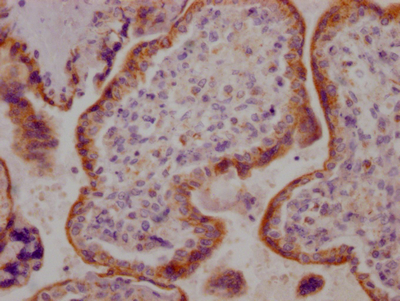

IHC image of CSB-RA260702A0HU diluted at 1:100 and staining in paraffin-embedded human breast cancer performed on a Leica BondTM system. After dewaxing and hydration, antigen retrieval was mediated by high pressure in a citrate buffer (pH 6.0). Section was blocked with 10% normal goat serum 30min at RT. Then primary antibody (1% BSA) was incubated at 4℃ overnight. The primary is detected by a Goat anti-rabbit IgG polymer labeled by HRP and visualized using 0.05% DAB.

CSB-RA260702A0HU

IHC image of CSB-RA260702A0HU diluted at 1:100 and staining in paraffin-embedded human placenta tissue performed on a Leica BondTM system. After dewaxing and hydration, antigen retrieval was mediated by high pressure in a citrate buffer (pH 6.0). Section was blocked with 10% normal goat serum 30min at RT. Then primary antibody (1% BSA) was incubated at 4℃ overnight. The primary is detected by a Goat anti-rabbit IgG polymer labeled by HRP and visualized using 0.05% DAB.